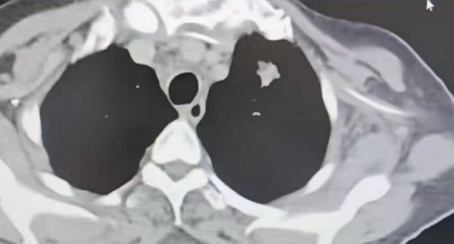

一位老年女性患者入院时卧床不起,伴有呼吸困难、胸闷憋喘、头痛等症状,确诊为左肺门占位性病变,合并纵隔淋巴结肿大、双肺炎症及颅脑转移,病情危重。葛新华主任团队全面评估后,采用动脉药物灌注联合栓塞治疗方案,将高浓度抗癌药物精准输送至肿瘤区域,同时栓塞供血动脉,在提升局部疗效的同时减轻全身副作用。经过两次规范治疗,患者症状显著改善,影像学复查显示双肺转移灶减少、纵隔淋巴结缩小,疗效达到完全缓解(CR)标准。